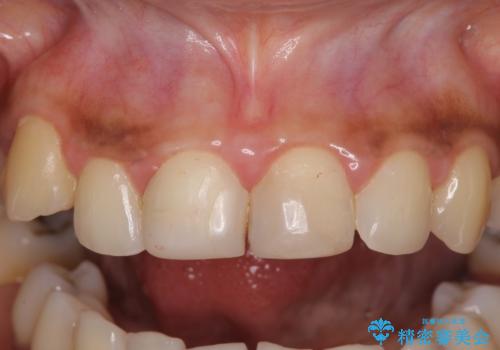

- 上の前歯2本の審美障害を気にして来院された患者様です。樹脂が無造作に充填されており、色合いも形態も不自然で、歯肉も腫れているため、オールセラミッククラウンにて補綴することとしました。

充填されたレジンを取り除いたところ、歯肉の炎症による出血が認められました。セラミッククラウン装着後は歯肉が腫れることもなく、仕上がりも自然な歯のようになり、患者様には大変満足していただきました。